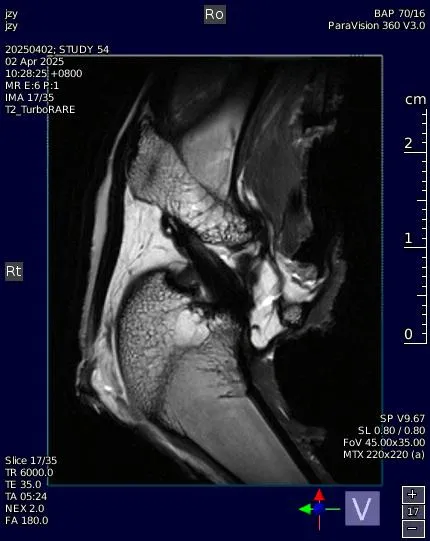

离体脑、关节、尾椎、肩胛骨等:推荐T2WI为主;

固定方式:多聚甲醛固定或新鲜冷冻;

注意事项:明确成像平面(冠状/矢状/横断面);固定后组织可能收缩10–20%。